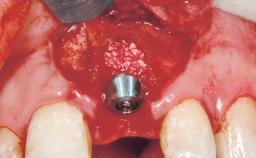

Late Flapless Placement of an Implant in a Maxillary Left Central Incisor Site

A 39-year-old male patient presented with a chief complaint of discomfort and gingival discoloration around his maxillary left central incisor. He was in good general health and was a non-smoker. His past dental history was significant because of the traumatic fracture of tooth 21 in a sporting accident at age 13. Initial dental treatment included endodontic therapy and a full-coverage restoration. The patient became symptomatic 5 years later, when structural failure of the tooth resulted in the dislodgment of the crown. Endodontic retreatment, apical surgery, and post-and-core restoration were performed.